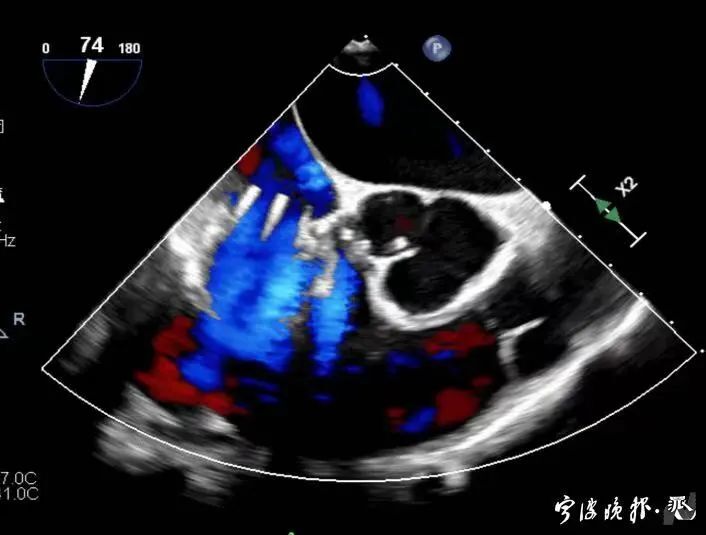

術后食道心超示三尖瓣反流消失